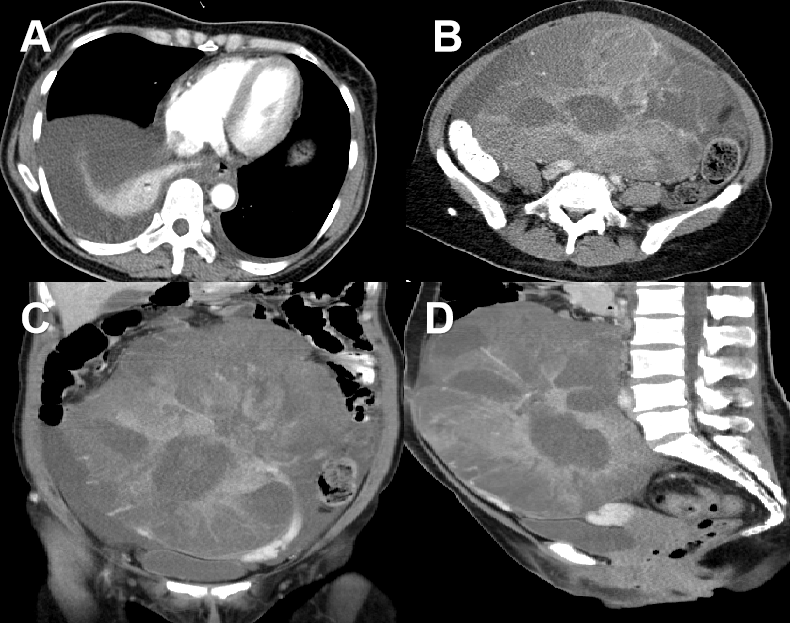

带着这些问题,医生对患者进行全面检查,发现几点有利的证据:①卵巢肿瘤巨大,但并没有包绕肠道和大血管,相对独立完整;②肠梗阻是由卵巢肿瘤巨大挤压导致的;③有胸腹水,但并没有发现病变,化疗过程胸腔积液未见明显减少。

这些发现,让患者的手术成为可能。最终经过一系列准备后,我院专家为患者取出了大小24×24×20厘米、7斤2两重的巨大肿块。术后第5天,患者的胸腹水也随之消失了。其病变提示为(腹盆腔)转移性腺癌,考虑为原肠癌转移。

最终,我院专家同样通过手术的方式,为患者完整切除24×24×20厘米的巨大肿块,术后3天,患者胸腔积液也消失。其病变也符合腹盆腔转移性腺癌,考虑为原肠癌转移。